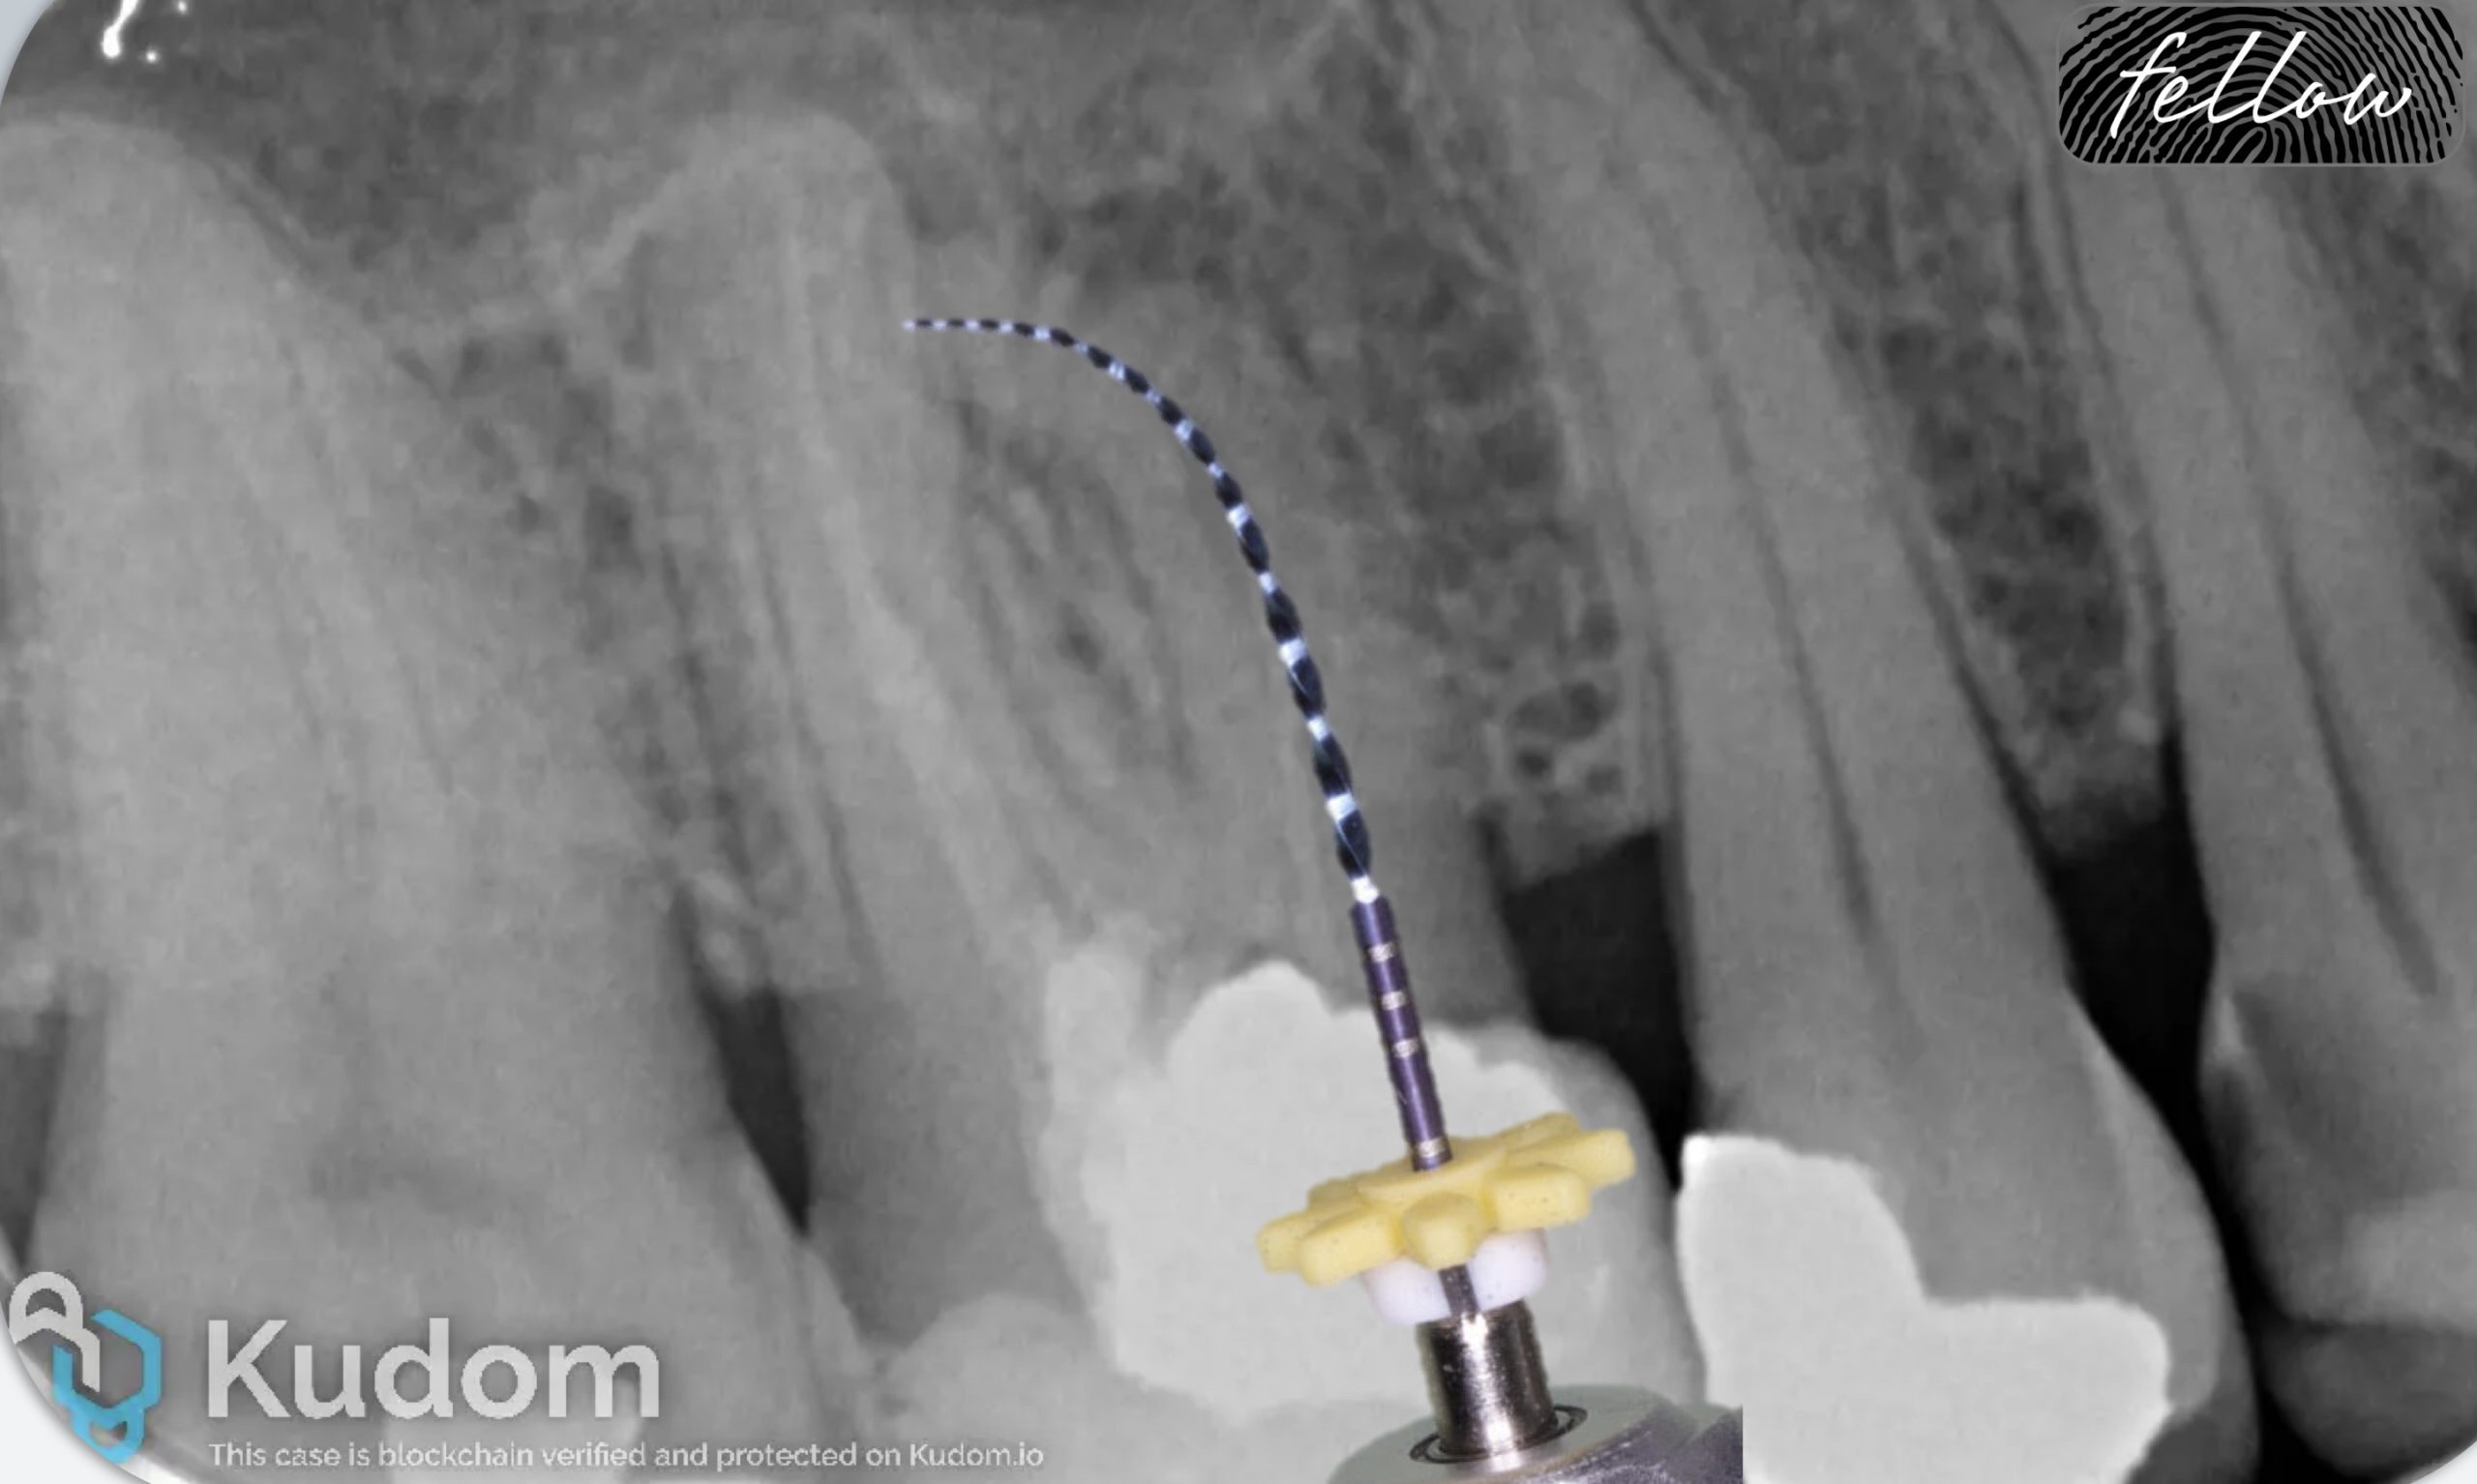

Advances in endodontic materials have influenced contemporary approaches to root canal obturation. A bioceramic sealers possess favorable properties, including biocompatibility, dimensional stability and the ability to form hydroxyapatite, which may enhance sealing root canal spaces. These characteristics have contributed to a shift toward simplified obturation techniques, particularly the single-cone approach. Compared with traditional compaction techniques, this method reduces procedural complexity and clinical time while maintaining an effective seal of the root canal system. For straightforward endodontic cases with adequate cleaning and shaping, simplified obturation protocols using bioceramic sealers have demonstrated predictable clinical outcomes.